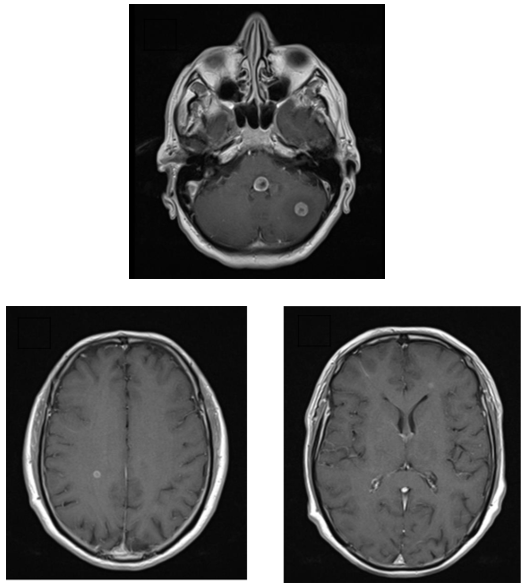

After admission for further investigation, autoimmune screen and serologies for HIV, HBV and HCV were found to be negative. A brain magnetic resonance imaging (MRI) was performed showing several lesions of nodular morphology, with hypersignal in T2 and FLAIR, with signal reinforcement after gadolinium administration (complete ring morphology) (Figure 1A). These lesions involved the posterior slope of the protuberance reaching the left facial nerve colliculi, the ipsilateral cerebellar hemisphere parenchyma, the white substance adjacent to the frontal horn of the left lateral ventricle, the white substance of the posterior third of the right semi-oval center and the cortex parasagittal frontal view on the same side (Figure 1B & 1C).

Figure 1: Brain MRI - Coronal T1 with gadolinium: A - Lesions with nodular morphology involving the left facial nerve colliculi and the ipsilateral cerebellar hemisphere parenchyma; B - Lesion involving the white substance of the posterior third of the right semi-oval center; C - Lesion involving the white substance adjacent to the frontal horn of the left lateral ventricle.